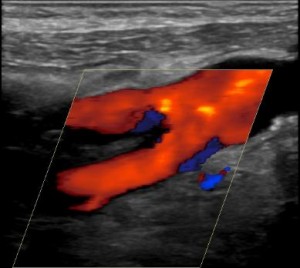

Duplex ultrasonography for imaging carotid arteries

Duplex ultrasound is a non invasive, safe and cheap method for imaging of blood vessels. The sensitivity of carotid duplex ultrasonography for detecting stenosis in the internal carotid artery is over 90{8ceaa46882e4d49283ff23b35262537230ad541262f55a031ead545e66522058} and so is the specificity. These figures become even more accurate in more severe disease (stenosis of over 70{8ceaa46882e4d49283ff23b35262537230ad541262f55a031ead545e66522058} versus 50{8ceaa46882e4d49283ff23b35262537230ad541262f55a031ead545e66522058}). Of note: duplex ultrasound is less accurate for diagnosing common carotid artery stenosis, but this disease is much less common and is therefore a less common cause of neurological symptoms.

Carotid duplex ultrasonography utilizes several measurement to estimate the degree of carotid stenosis:

- Internal carotid artery peak systolic velocity (ICA PSV) – Peak systolic velocity increases as stenosis increases, if it is hemodynamically significant.

- Plaque estimate

- The internal carotid / common carotid peak systolic velocity ratio

- Internal carotid artery end diastolic velocity (ICA EDV)

Every carotid duplex ultrasound examination has the following components:

- Visualization of the common carotid, external carotid, internal carotid and vertebral arteries – bilaterally.

- Imaging is performed separately for imaging (‘B mode’) and doppler (because different tube angles are used (90 degrees for the B mode versus 60 degrees for the doppler).

- Images are obtained in sagital and transverse views.

- Plaque size, location and composition are evaluated.